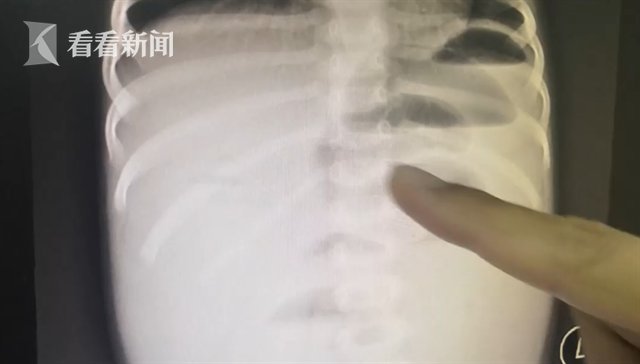

深圳市儿童医院普外一科医生储冬冬说:“可以看到她出现了一个很明显的肠梗阻,就是上面的肠子扩张得很明显,底下的肠子已经完全没有气了,就是一个空扁的状态。这个就是提示我们她的肠梗阻很严重,有急诊手术的体征。消化道里面有一个异物是球形的。已经把肠子完全塞住了。”医生认为,乐乐的情况不能保守治疗了,需要开刀把异物取出,不然就会危及到生命危险了。